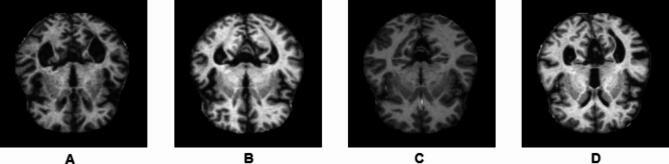

Alzheimer's disease (AD) is one of the primary causes of dementia in the older population, affecting memories, cognitive levels, and the ability to accomplish simple activities gradually. Timely intervention and efficient control of the disease prove to be possible through early diagnosis. The conventional machine learning models designed for AD detection work well only up to a certain point. They usually require a lot of labeled data and do not transfer well to new datasets. Additionally, they incur long periods of retraining. Relatively powerful models of deep learning, however, also are very demanding in computational resources and data. In light of these, we put forward a new way of diagnosing AD using magnetic resonance imaging (MRI) scans and transfer learned convolutional neural networks (CNN). Transfer learning makes it easier to reduce the costs involved in training and improves performance because it allows the use of models which have been trained previously and which generalize very well even when there is very little training data available. In this research, we used three different pre-trained CNN based architectures (AlexNet, GoogleNet, and MobileNetV2) each implemented with several solvers (e.g. Adam, Stochastic Gradient Descent or SGD, and Root Mean Square Propagation or RMSprop). Our model achieved impressive classification results of 99.4% on the Kaggle MRI dataset as well as 98.2% on the Open Access Series of Imaging Studies (OASIS) database. Such results serve to demonstrate how transfer learning is an effective solution to the issues related to conventional models that limits the accuracy of diagnosis of AD, thus enabling their earlier and more accurate diagnosis. This would in turn benefit the patients by improving the treatment management and providing insights on the disease progression.

阿尔茨海默病(AD)是老年人群痴呆症的主要病因之一,会逐渐影响记忆、认知水平以及完成简单活动的能力。通过早期诊断可以实现对该疾病的及时干预和有效控制。为AD检测设计的传统机器学习模型在一定程度上效果良好。它们通常需要大量的标注数据,并且不能很好地迁移到新数据集。此外,它们需要长时间重新训练。然而,相对强大的深度学习模型对计算资源和数据的要求也很高。鉴于此,我们提出了一种利用磁共振成像(MRI)扫描和迁移学习卷积神经网络(CNN)来诊断AD的新方法。迁移学习使得降低训练成本和提高性能变得更加容易,因为它允许使用先前训练过的模型,这些模型即使在可用训练数据很少的情况下也能很好地泛化。在本研究中,我们使用了三种不同的基于预训练CNN的架构(AlexNet、GoogleNet和MobileNetV2),每种架构都用几种求解器(如Adam、随机梯度下降或SGD以及均方根传播或RMSprop)来实现。我们的模型在Kaggle MRI数据集上取得了令人印象深刻的99.4%的分类结果,在开放获取影像研究系列(OASIS)数据库上也达到了98.2%。这些结果证明了迁移学习是解决与传统模型相关问题的有效方法,这些问题限制了AD诊断的准确性,从而能够实现对AD的更早、更准确的诊断。这反过来将通过改善治疗管理并提供有关疾病进展的见解而使患者受益。